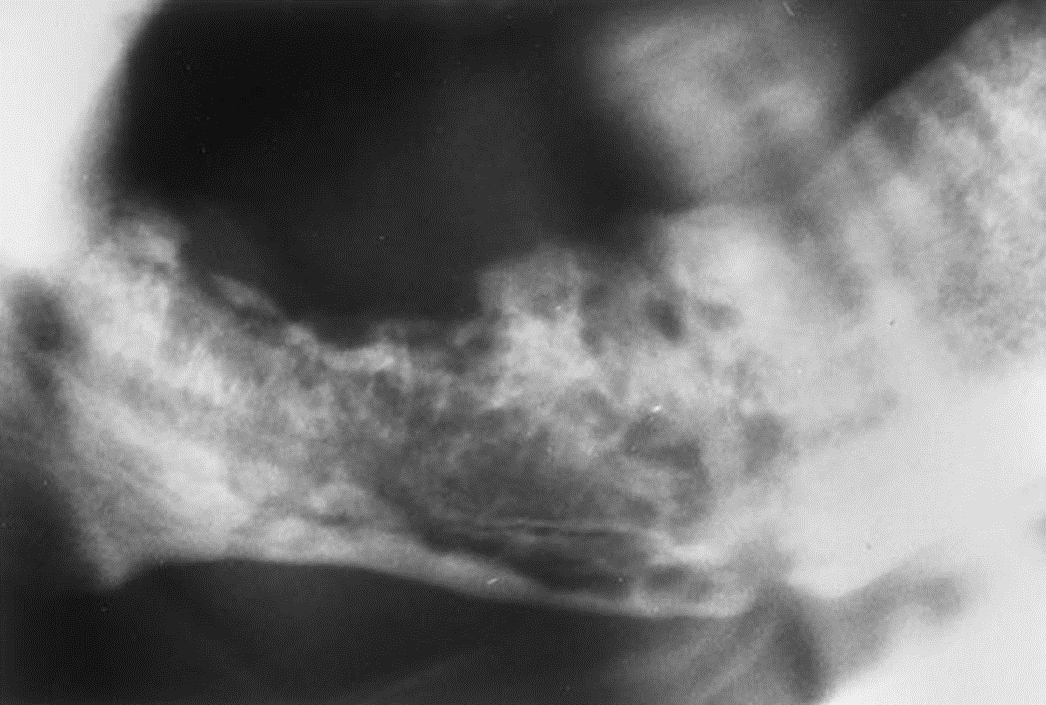

3. This is a 35-year-old asymptomatic woman who has slight buccal and palatal enlargement of the alveolar bone in this area. Other studies indicated portions of the zygoma were involved. This condition was first detected at age 19 years and is slowly progressive. Her alkaline phosphatase was normal to high-normal, and her serum calcium was normal.

What is your diagnostic impression?